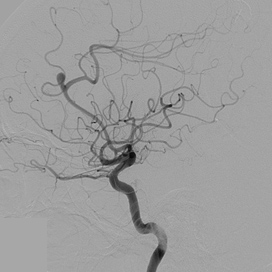

뇌혈관 조영술 |